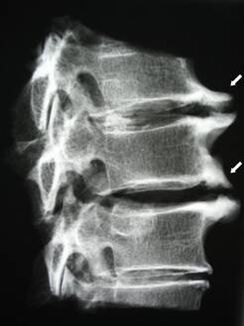

V počátečních stádiích je osteochondróza detekována pomocí MRI. Později může být patologie diagnostikována pomocí radiografie. Na rentgenových snímcích krční páteře je patrné snížení vzdálenosti mezi obratli, patologické změny ve fasetových kloubech a osteofytóza.

| Cervikální osteochondróza | Výskyt patologických změn v jednom nebo více segmentech pohybu páteře. Porucha pohyblivosti páteře, rozvoj myofasciálních bolestivých syndromů a skřípnutí míšních kořenů | Bolest, parestézie a motorické poruchy v cervikální oblasti, které se šíří do zadní části hlavy a horních končetin. Detekce charakteristických změn páteře na MRI a rentgenových snímcích (osteofyty, zmenšená vzdálenost mezi obratli, známky poškození meziobratlových kloubů) |